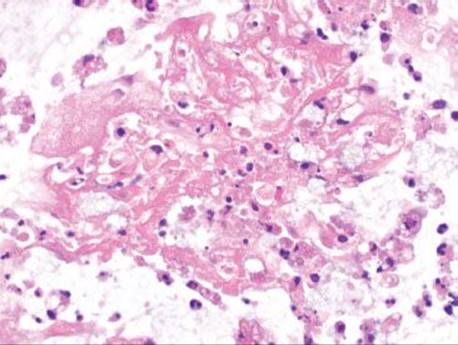

Figure 4.84 Pseudomembranous pattern, marked. Severe cases of pseudomembranous colitis may require colectomy, as in this case. There is extensive tissue necrosis and only rare residual crypts (arrowheads) remain.